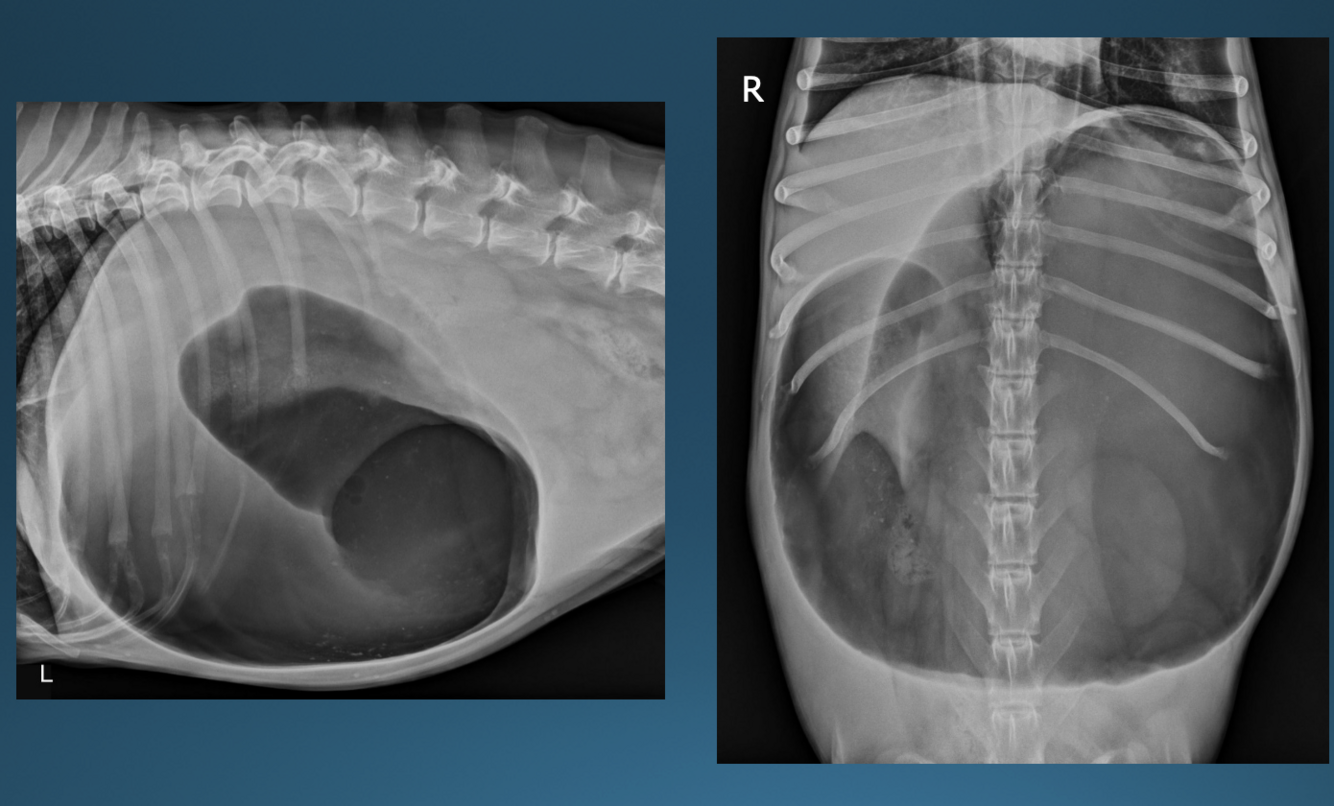

What is shown in these images?

canine acute gastric outflow obstruction:

-stomach slightly distended with fluid and gas

-hard to see stomach margins